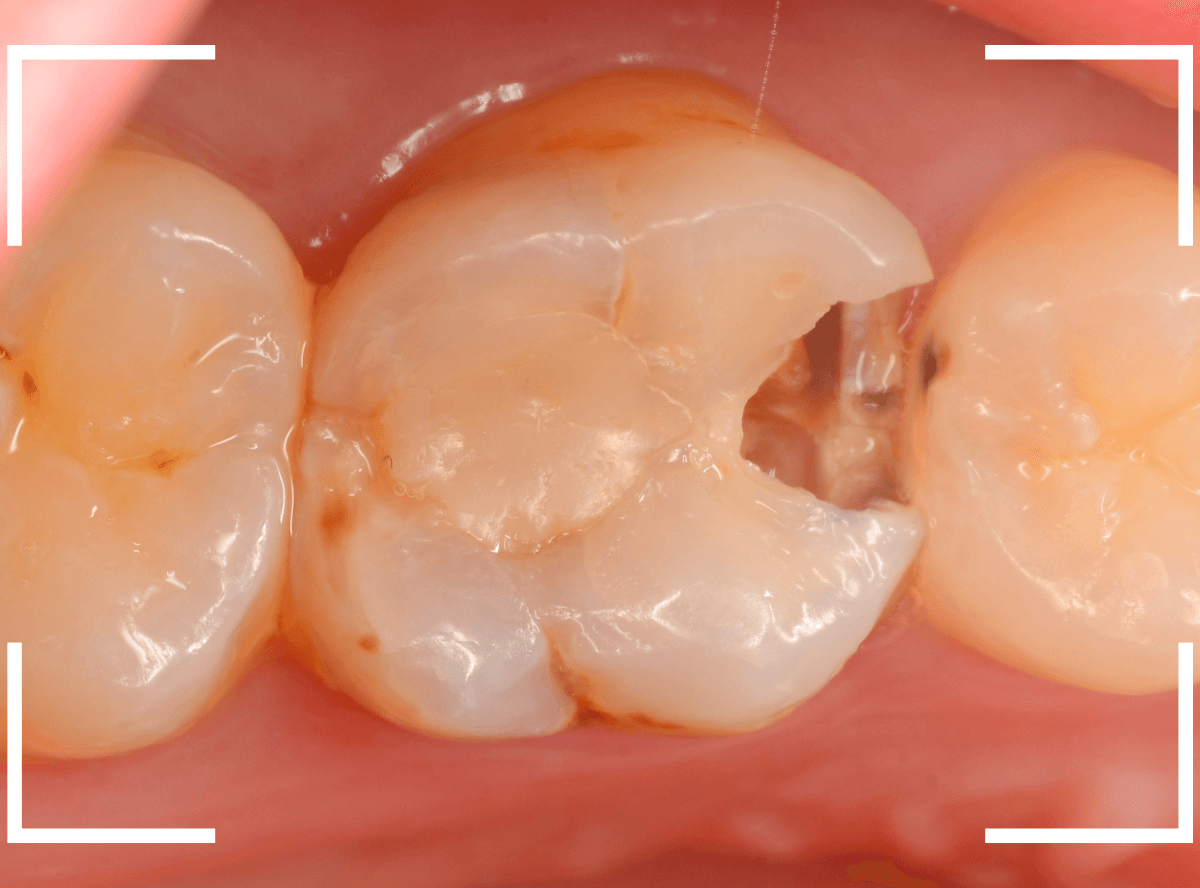

抜歯してしばらく経ったところです。

特に問題なさそうに見えますが、「おやしらずを抜歯してから、歯がしみるようになった」との訴えです。

これは、おやしらずを抜歯した後によくある症状です。